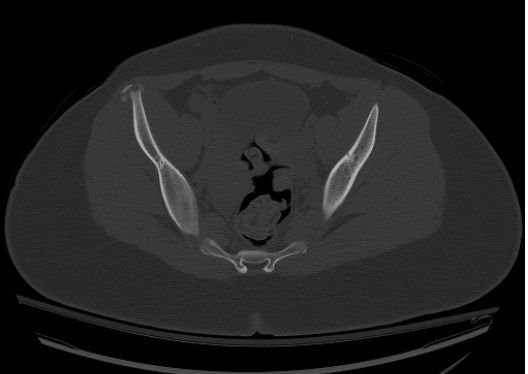

What injury could be related to this anterior superior iliac spine avulsion injury? What's your diagnosis?

What is your diagnosis?